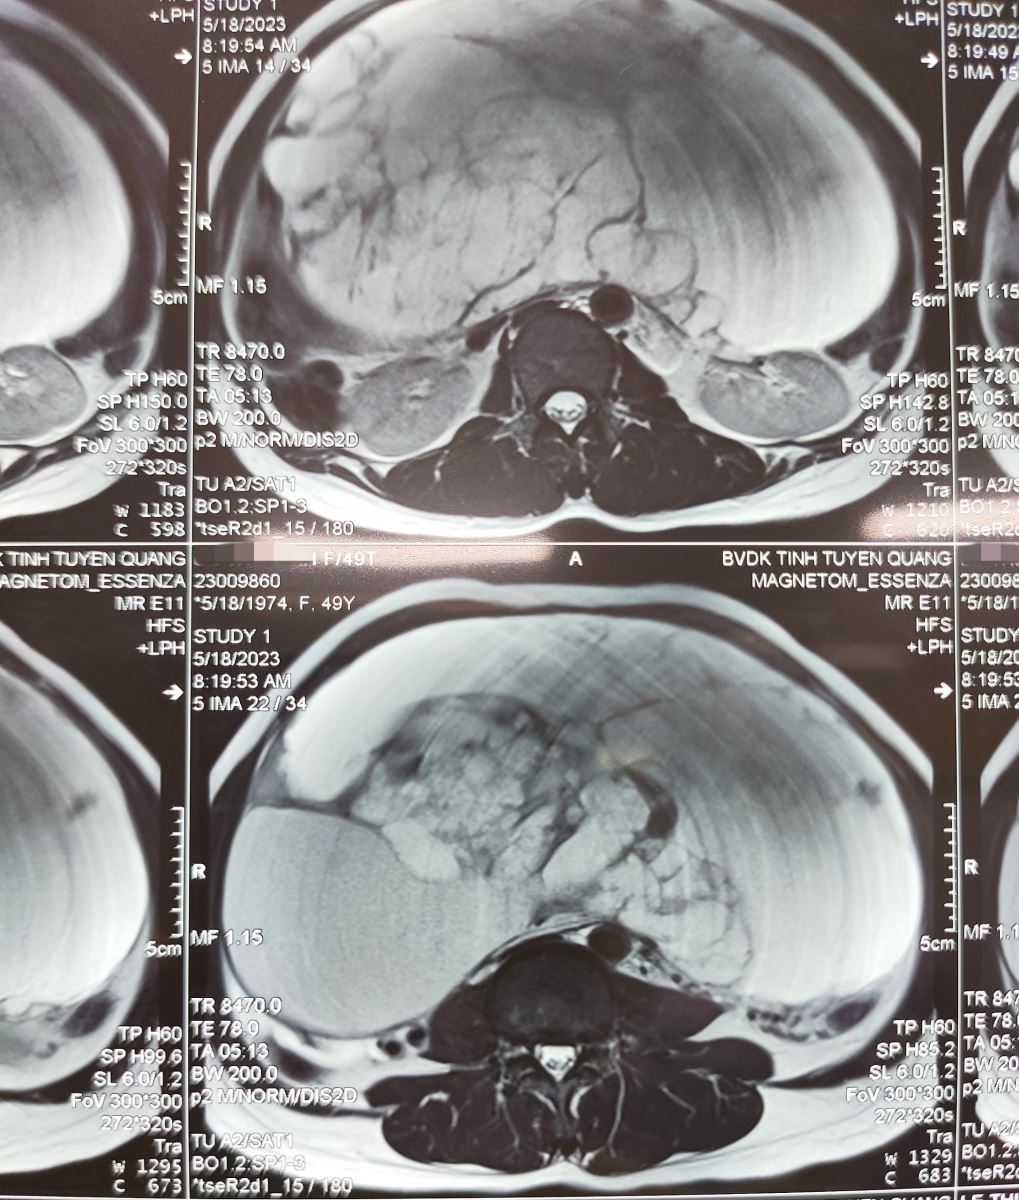

Sau khi được các bác sỹ thăm khám và làm các cận lâm sàng cần thiết, bệnh nhân đã được chẩn đoán có u buồng trứng khổng lồ, kích thước khoảng (25,6x15,7x29,8 cm). Sau khi hội chẩn liên chuyên khoa, bệnh nhân được chuyển về khoa Ung bướu để điều trị và phẫu thuật.

Hình ảnh chụp Cộng hưởng từ (MRI) khối u chiếm gần hết ổ bụng bệnh nhân. Ảnh BVCC

Khối u đã được cắt khỏi ổ bụng của bệnh nhân nặng 6,6kg, chiếm toàn bộ ổ bụng, chèn ép các cơ quan nội tạng khác trong ổ bụng, gây đau và nguy hiểm cho bệnh nhân.